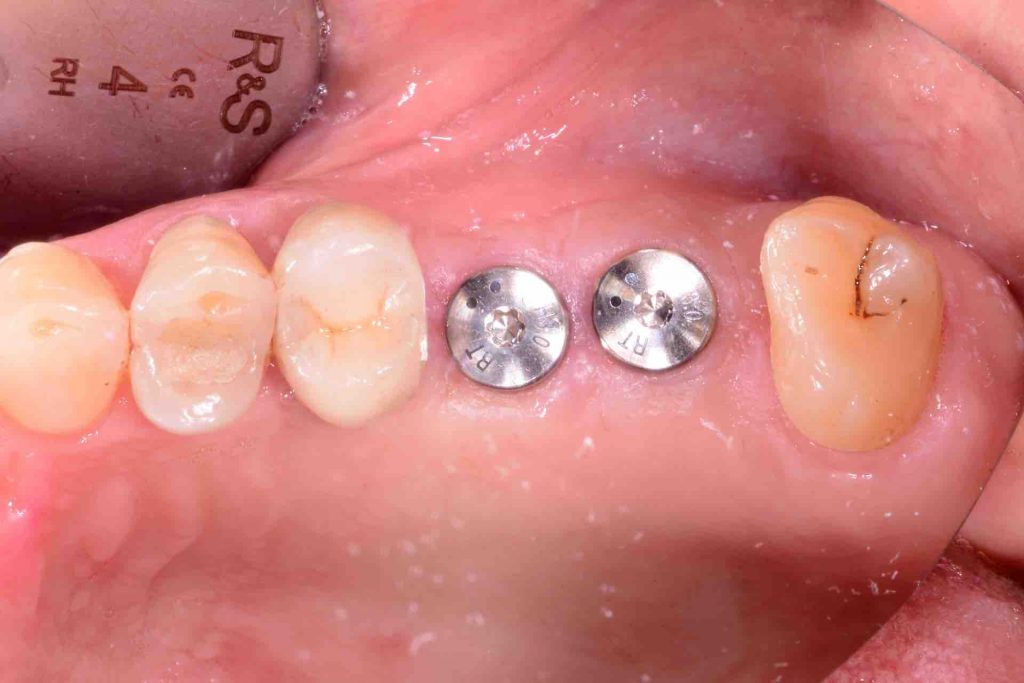

- Two 8 mm Straumann TLX implants placed

occlusal view, implants placed

7-days healing

1 week follow-up

one month follow-up